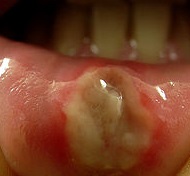

It is pretty easy to spot a canker sore, considering that they look unusual in the mouth. They are either round or oval in shape, with their centers colored yellow or white. Since these are sores, their borders are inflamed with a red color. They can be found almost anywhere in your mouth–inside the cheek, on the tongue or under it, beneath the lips, or even on the gums.(8*)

There are three types of canker sores. The minor canker sores are the most common ones, measuring around 3-10 mm. only. They are yellowish in color, with a red halo circling them. Although it disappears in about two weeks, they can be quite painful.(10*)